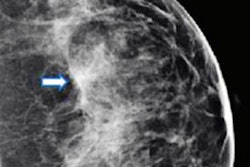

Images show screen-detected invasive breast cancer in dense breast tissue in a 65-year-old woman. The histology was invasive carcinoma of no special type with a tumor size of 10 mm, grade 2. (A) A single section of a DBT scan of the craniocaudal view of the right breast shows a cancer-related spiculated mass with highly suspicious radiologic features (arrow). (B) Corresponding synthesized mammogram of the right craniocaudal view shows that the cancer-related spiculation is less obvious in comparison to the single section (arrow). (C) Correlating ultrasound scan shows the invasive breast cancer as an irregular, indistinct, not parallel, hypoechoic mass (arrow) with a hyperechoic distortion of the adjacent parenchyma. Images courtesy of RSNA.However, in this most recent study, the team wanted to focus on comparing the invasive breast cancer detection rate of the combined approach versus digital mammography for women with different breast density categories.